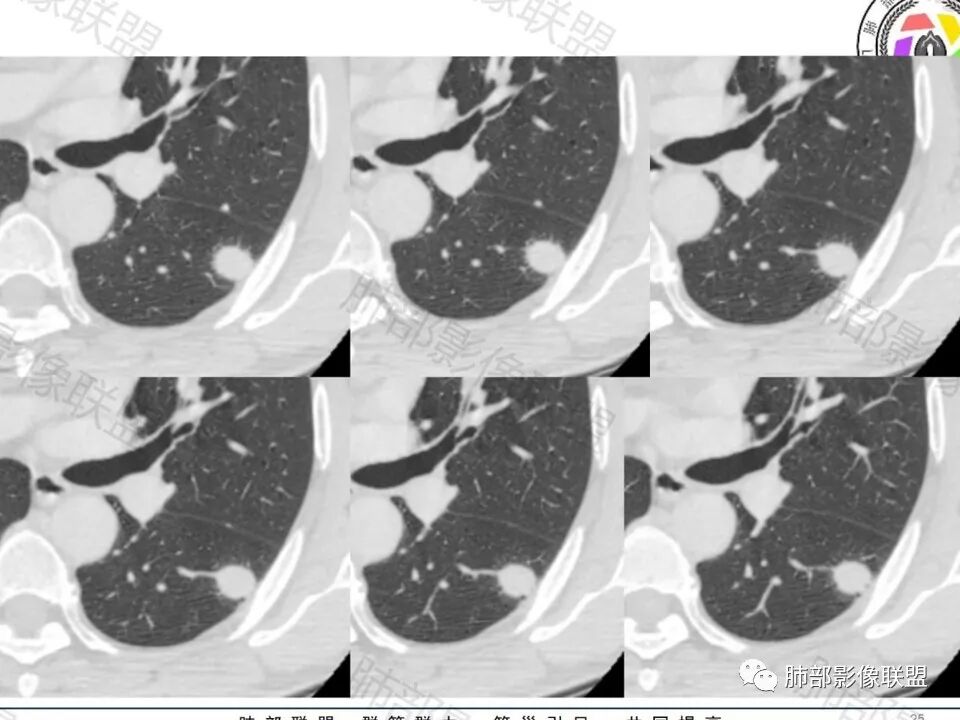

老年男性,无症状,肺气肿背景

这个囊可靠吗?

这应该是附近的肺气肿

血管进去还是比较自然

南边:

类圆形,边缘稍平直,周围晕中细微毛刺,密度均匀,均匀强化,血管走形自然,稍牵拉扭曲,支气管在近端堵塞

多发类似结节

常规思路:

1、炎性结节,多发,类似,晕,隐球菌?

2、恶性:多发:转移瘤?肺癌并多发转移瘤?

大家目前碰到多数结节是磨玻璃结节,对于实性结节的诊断反而陌生,其实性结节才是考验脑子的时候;

这枚结节的纵隔窗在没有调节窗位的情况下,已经很密实了,说明这个结节里面是软组织的成分,这与普通炎性结节(隐球菌等)的密度还是有区别的,很多年前就有人提出,纵隔窗显示越大,恶性可能越大;

结节周围有磨玻璃影,边界似清不清的,但是总体不如炎性晕征那么模糊;

增强的程度很难讲,但是不均匀强化是可以确定的;

有收缩力,但是很轻,按照常理,实性结节因为有占位效应,不太会有收缩力,但是叶间胸膜有凹陷。所以讲,这个结节还是开了放心。